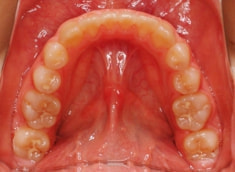

治療後(1年2ヶ月後)